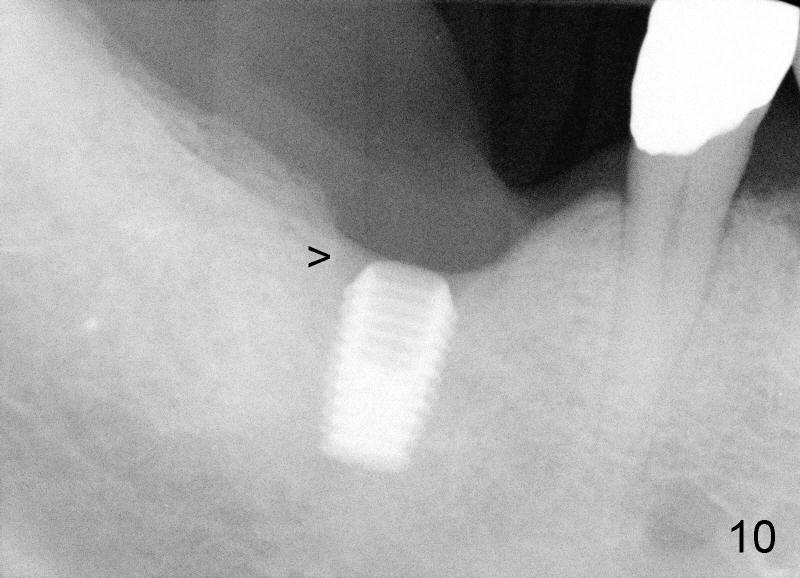

Three months later, the wound heals. X-ray shows that bone loss distal to the implant (Fig.6 double arrowheads) disappears, similar to the one taken another two months later (Fig.10), when the implant is uncovered. The circumferential bone loss shown in Fig.8 is reduced to the distal crest of the implant at the time of uncovering (data not shown).